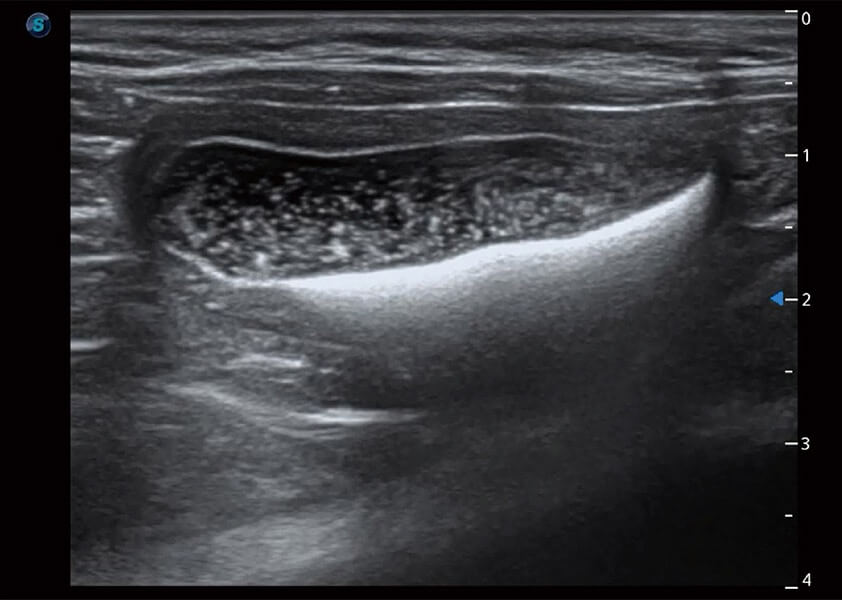

ProPet 60 作为一款高端台式动物超声设备,为动物医生的日常诊断提供了一系列贴合动物临床需求、解决临床实际问题的高级成像功能。凭借全系列高清探头,满足医生对腹部、心脏、生殖、浅表、肌骨等成像的所有需求,切实帮助您提升检查效率,提高诊断信心。

动物是人类最亲密的朋友和最值得信赖的伙伴。米兰官方网站也一直致力于探索动物专用的超声影像解决方案。 全新推出的ProPet系列,是米兰官方网站在动物超声影像智能化、专业化、精准化的一次跨越式革新。动物不能用言语来表述自己的不适,通过超声影像,ProPet系列搭建了动物医生与不同物种沟通的“桥梁”,为动物医生注入了“治愈之力”。